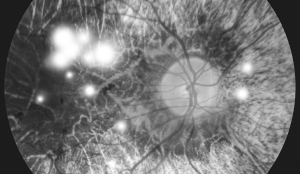

• Proliferative Diabetic Retinopathy (PDR)

Proliferative Diabetic Retinopathy (PDR)

Abnormal blood vessels grow on the optic nerve's surface, causing frequent bleeding and scar formation, which can lead to retinal detachment and, in severe cases, blindness.